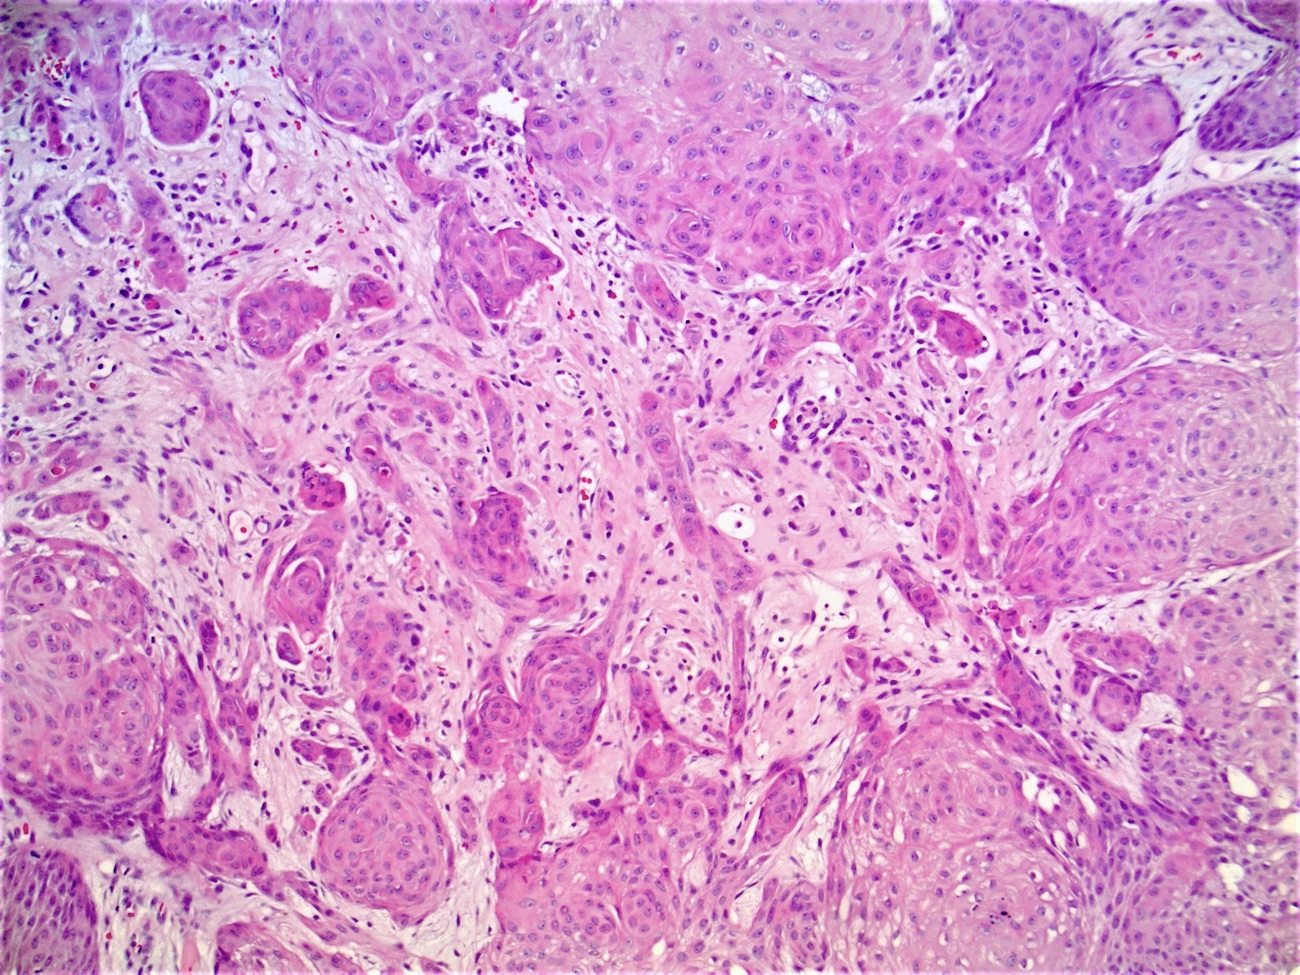

- Well circumscribed, endophytic tumor with large lobules or finger-like extensions that resemble expanded follicles

- Variable number of squamous eddies

- Occasional mitoses within peripheral basaloid cells

Microscopic (histologic) images